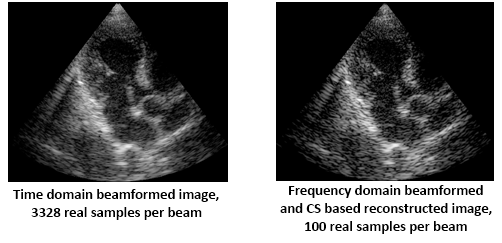

Further reduction in sampling rate is obtained when only a portion of the beam’s bandwidth is used [1]. In this case the detected signals are sampled at a sub-Nyquist rate, leading to up to 28 fold sampling rate reduction per element. In order to reconstruct the beamformed signal from its partial frequency data, we rely on the fact that the beamformed signal obeys a finite rate of innovation (FRI) model and use Compressed Sensing (CS) techniques [2],[3].

In our laboratory, frequency domain beamforming is implemented on a state of the art ultrasound machine [4]. Low-rate processing is performed on a 64-element cardiac probe. We demonstrate our methods on in vivo cardiac data and show that reduction up to 1/28 over standard beamforming rates is achievable.

Images obtained by time domain vs. frequency domain beamforming are shown in Fig. 4. The images are virtually identical, while 8 fold savings in sampling and processing rates was achieved using frequency domain beamforming.

Further rate reduction is achieved when the detected signals are sampled at a sub-Nyquist rate. In this case beamforming in frequency yields a subset of beamformed signal frequency components. To recover the beam from its partial frequency data we exploit the signal's structure that was not considered so far, by using ideas of Xampling and FRI. The important point is that both sampling and beamforming are performed at a low rate.